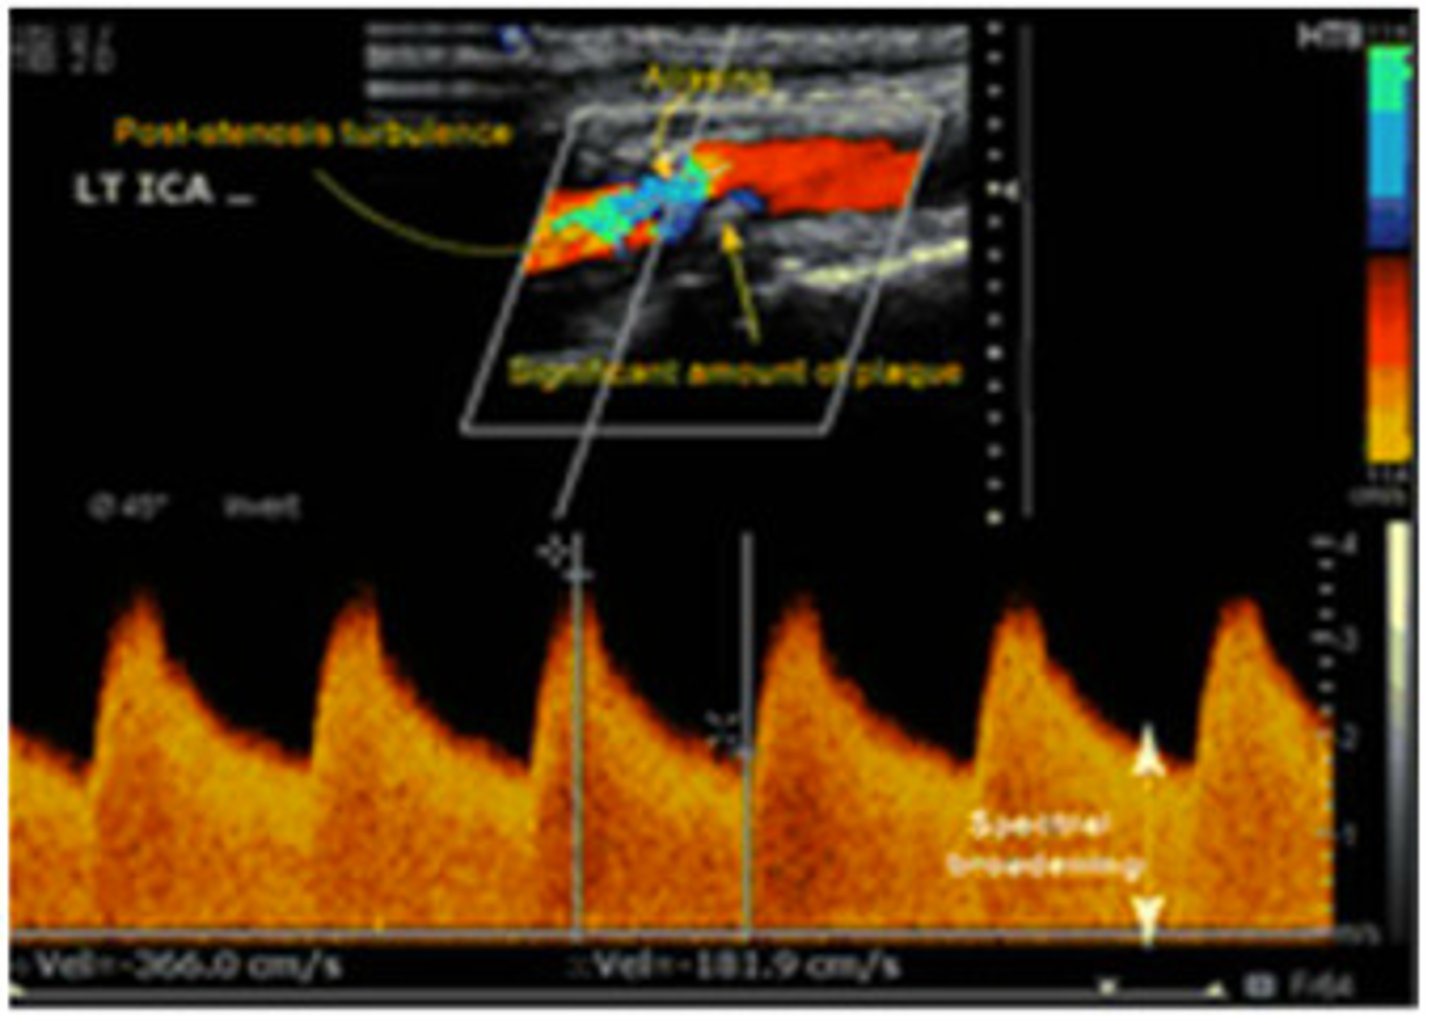

The appearance of the spectral Doppler waveform and the velocity recorded in this image represents...

no stenosis

mild stenosis

significant stenosis

total occlusion